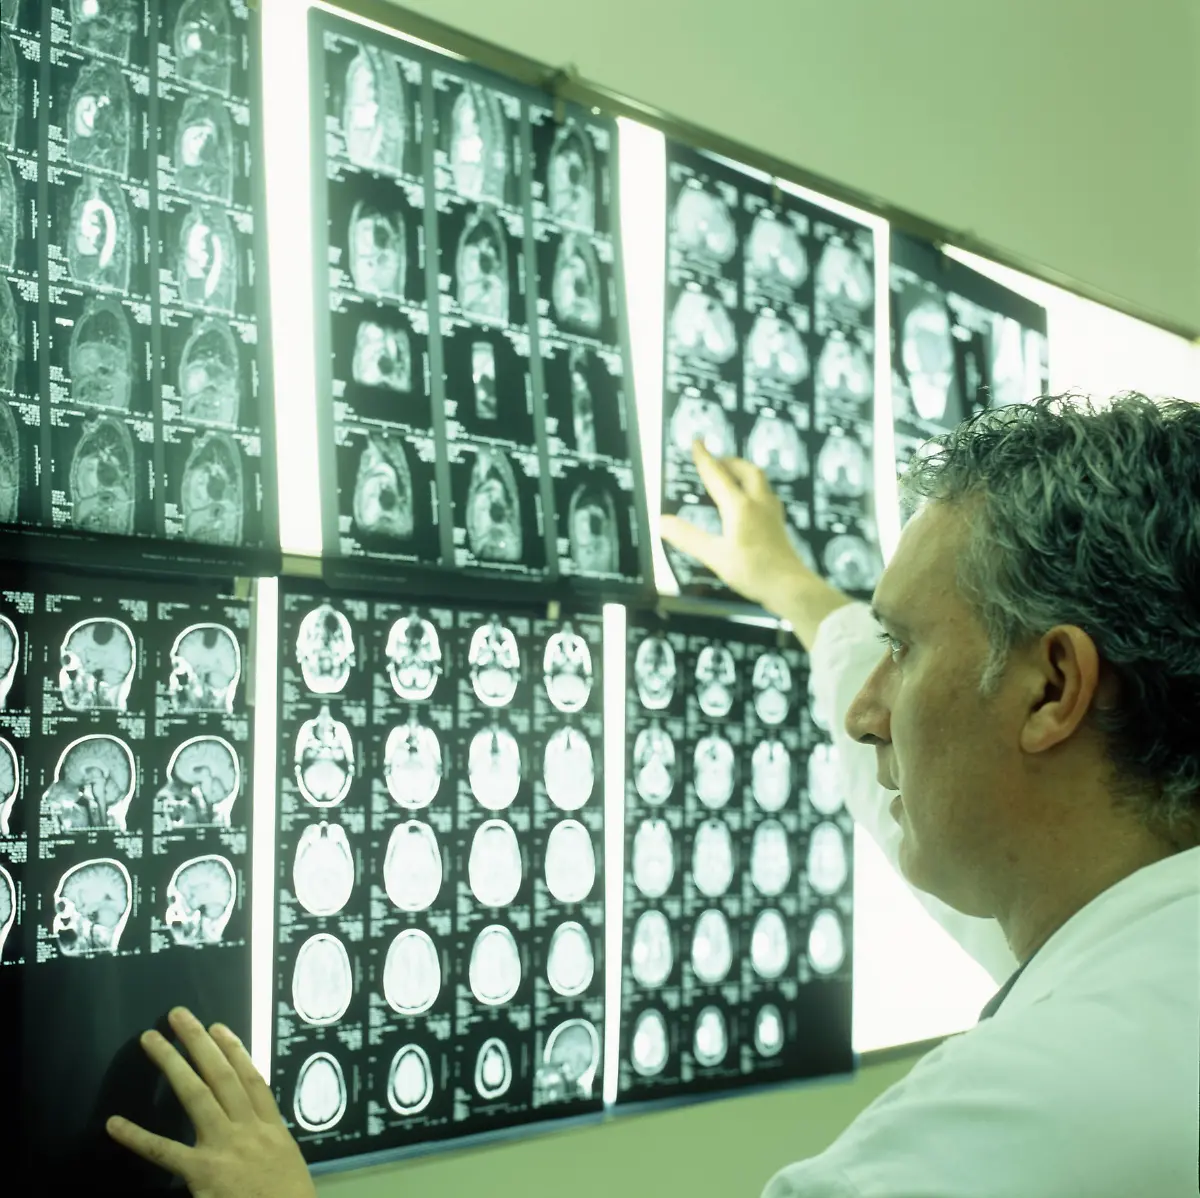

Egal, ob es ums Sehen oder Hören geht, ums Atmen, Sprechen, Rechnen oder Laufen: Stets sind es Milliarden grauer Zellen, die diese Fähigkeiten ermöglichen. Viele verschiedene Bereiche des Gehirns arbeiten zusammen, um die unterschiedlichsten Aufgaben zu lösen. Was wird von wo gesteuert? n-tv.de erklärt, was es mit Frontallappen, Mandelkern & Co. auf sich hat.